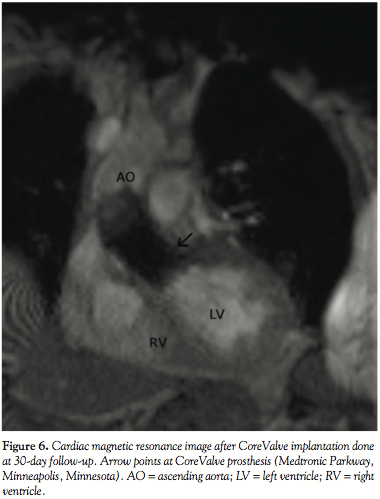

The patient was kept in the intensive care unit for 3 more days and then transferred to the department for further management and rehabilitation. She reported rapid relief of her symptoms with marked improvement in her functional capacity (Figure 2B). Dual antiplatelet therapy (aspirin 100 mg/day and clopidogrel 75 mg/day) was advised for 6 months, and aspirin was prescribed lifelong. Thirty-day follow-up echocardiography revealed a well functioning

prosthetic aortic valve with an estimated valve area of 2.1 cm2 and a mean gradient of 12 mmHg. Cardiac magnetic resonance was performed for evaluating the CoreValve function and revealed mild aortic regurgitation with a retrograde volume of 5.96 ml (Figure 6). At 6 months, the patient continued to be symptom-free and the prosthetic aortic valve was functioning appropriately.